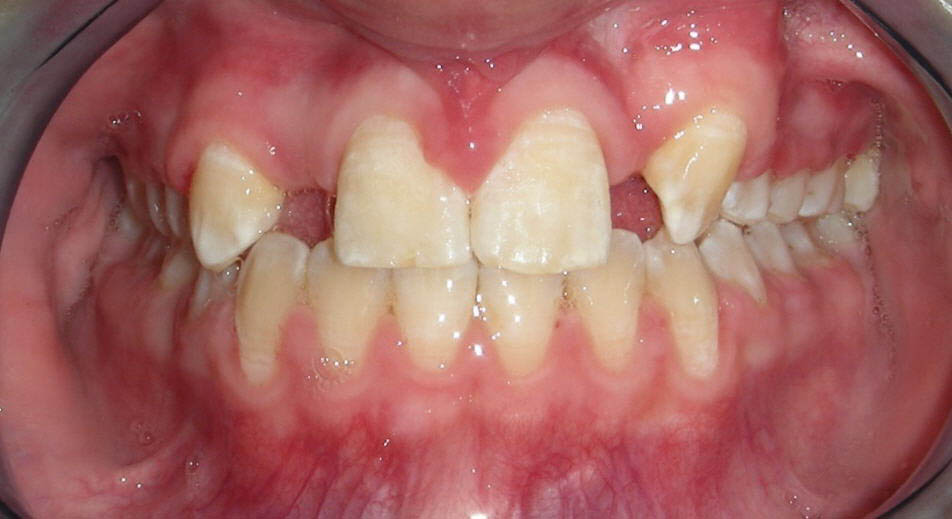

A doua etapă a tratamentului a fost amânată până în aprilie 2006, când pacienta a împlinit vârsta de 11 ani şi 5 luni. În acel moment, fetiţa prezenta erupţie şi dezvoltare radiculară adecvată, astfel că aparatele fixe aplicate acum n-ar fi purtate o perioadă îndelungată. Ocluzia inversă frontală şi angrenajul invers lateral fuseseră corectate; totuşi, exista o diastemă mare, în principal cauzată de lipsa incisivilor laterali superiori (fig.3). În acest moment, radiografia panoramică relevă anodonţia incisivilor laterali maxilari şi a premolarului secund drept mandibular, o anatomie redusă a rădăcinilor incisivilor centrali superiori, incluzia caninului superior stâng şi dezvoltarea întârziată a rădăcinii celui de-al doilea premolar inferior (fig. 4).